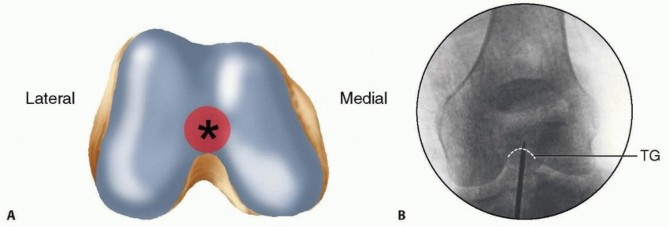

---  ### FIG 1 • A. Distal femur viewed end on, with ideal starting point for retrograde femoral nailing identified (asterisk) just anterior to the posterior cruciate ligament insertion. B,C. AP and lateral radiographs of the knee, with the initial starting guidewire positioned at the ideal starting point for retrograde femoral nailing. The radiographic landmark for the trochlear groove (TG) is indicated on the AP radiograph and for the line of Blumensaat (BL) on the lateral radiograph. Pertinent proximal anatomy includes neurovascular structures anterior to the proximal femur, close to interlocking screw insertion sites. 24 The femoral artery is medial to the proximal femur, with branches that cross the anterior femur more than 4 cm distal to the lesser trochanter. Branches of the femoral nerve cross more proximal starting 4 cm distal to the piriformis fossa. Damage to neurovascular structures caused by proximal locking screw insertion can be avoided or minimized by avoiding medial dissection and with placement at or above the lesser trochanter ( FIG 2). ## PATHOGENESIS Femoral shaft fractures are markers of high-energy injuries. 10, 12, 13, 14, 23, 27 Studies have shown that 38% of trauma patients diagnosed with a femoral shaft fracture have additional injuries. 3, 7, 8, 26 In femur fracture patients with associated injuries, the most common findings are other musculoskeletal injuries (93%), thoracic injuries (62%), head injuries (59%), abdominal injuries (35%), and facial injuries (16%). 7

### FIG 1 • A. Distal femur viewed end on, with ideal starting point for retrograde femoral nailing identified (asterisk) just anterior to the posterior cruciate ligament insertion. B,C. AP and lateral radiographs of the knee, with the initial starting guidewire positioned at the ideal starting point for retrograde femoral nailing. The radiographic landmark for the trochlear groove (TG) is indicated on the AP radiograph and for the line of Blumensaat (BL) on the lateral radiograph. Pertinent proximal anatomy includes neurovascular structures anterior to the proximal femur, close to interlocking screw insertion sites. 24 The femoral artery is medial to the proximal femur, with branches that cross the anterior femur more than 4 cm distal to the lesser trochanter. Branches of the femoral nerve cross more proximal starting 4 cm distal to the piriformis fossa. Damage to neurovascular structures caused by proximal locking screw insertion can be avoided or minimized by avoiding medial dissection and with placement at or above the lesser trochanter ( FIG 2). ## PATHOGENESIS Femoral shaft fractures are markers of high-energy injuries. 10, 12, 13, 14, 23, 27 Studies have shown that 38% of trauma patients diagnosed with a femoral shaft fracture have additional injuries. 3, 7, 8, 26 In femur fracture patients with associated injuries, the most common findings are other musculoskeletal injuries (93%), thoracic injuries (62%), head injuries (59%), abdominal injuries (35%), and facial injuries (16%). 7  ---

---  ### FIG 2 • Cross-sectional view of the proximal femur, with proximal interlocking screw insertion shown and pertinent medial neurovascular structures. Ipsilateral femoral neck fractures occur in 1% to 6% of all femoral shaft fractures and are initially missed in up to 20% to 50% of cases. 29 Recognition of these injuries before intramedullary stabilization is important to minimize potential complications (refer to section on Imaging and Other Diagnostic Studies). All trauma patients should undergo the standard advanced trauma life support (ATLS) examination to rule out associated life-threatening injuries. Although less common, femoral shaft fractures can occur in isolated sports injuries and in low-energy injuries associated with pathologic bone, such as with osteoporosis or metastatic bone disease. ## PATIENT HISTORY AND PHYSICAL FINDINGS Pain and deformity of the thigh are usually obvious but may be obscured in the morbidly obese patient. The fractured limb should be closely examined to avoid missing any open wounds, particularly in the posterior aspect of the thigh. Skin abrasions and apparently minor wounds should be assessed to determine if they communicate with the fracture. Swelling is a common finding with femoral shaft fractures. Compartment syndrome of the thigh is rare but can occur. 28 The entire lower extremity and pelvis needs to be evaluated because of the high rate of associated musculoskeletal injuries. A thorough neurologic and vascular examination must also be performed. Although femoral nerve damage is very unusual, sciatic nerve damage can occur. 4, 6, 34 Associated ligamentous injuries of the knee are common but may be difficult to assess until definitive stabilization of the femur has been obtained. Therefore, this examination should be repeated after nailing the femoral fracture. 31, 32 ## IMAGING AND OTHER DIAGNOSTIC STUDIES AP and lateral radiographs of the full length of the femur are essential, as well as formal AP and lateral radiographs of the hip and knee. Lateral knee radiographs should be closely evaluated for subtle patellar impaction fractures or nondisplaced fractures. Hip radiographs should be closely examined to rule out an associated femoral neck fracture, which has been shown to occur in 1% to 6% of femoral shaft fractures. 29 Some surgeons recommend a routine computed tomography (CT) scan examination of the femoral neck as part of the trauma scan to rule out a femoral neck fracture. A reported 20% to 50% of these injuries are missed on the initial plain radiographic examination. 29 Because of the high association of missed coronal fractures in high-energy injuries, a CT scan of the knee should be obtained whenever formal knee radiographs reveal a supracondylar distal femur fracture and there is consideration for retrograde nailing. 17 Any coronal fractures seen on CT examination should be considered a contraindication for retrograde nailing owing to the possibility of compromising the distal interlocking screw fixation. ## SURGICAL MANAGEMENT

### FIG 2 • Cross-sectional view of the proximal femur, with proximal interlocking screw insertion shown and pertinent medial neurovascular structures. Ipsilateral femoral neck fractures occur in 1% to 6% of all femoral shaft fractures and are initially missed in up to 20% to 50% of cases. 29 Recognition of these injuries before intramedullary stabilization is important to minimize potential complications (refer to section on Imaging and Other Diagnostic Studies). All trauma patients should undergo the standard advanced trauma life support (ATLS) examination to rule out associated life-threatening injuries. Although less common, femoral shaft fractures can occur in isolated sports injuries and in low-energy injuries associated with pathologic bone, such as with osteoporosis or metastatic bone disease. ## PATIENT HISTORY AND PHYSICAL FINDINGS Pain and deformity of the thigh are usually obvious but may be obscured in the morbidly obese patient. The fractured limb should be closely examined to avoid missing any open wounds, particularly in the posterior aspect of the thigh. Skin abrasions and apparently minor wounds should be assessed to determine if they communicate with the fracture. Swelling is a common finding with femoral shaft fractures. Compartment syndrome of the thigh is rare but can occur. 28 The entire lower extremity and pelvis needs to be evaluated because of the high rate of associated musculoskeletal injuries. A thorough neurologic and vascular examination must also be performed. Although femoral nerve damage is very unusual, sciatic nerve damage can occur. 4, 6, 34 Associated ligamentous injuries of the knee are common but may be difficult to assess until definitive stabilization of the femur has been obtained. Therefore, this examination should be repeated after nailing the femoral fracture. 31, 32 ## IMAGING AND OTHER DIAGNOSTIC STUDIES AP and lateral radiographs of the full length of the femur are essential, as well as formal AP and lateral radiographs of the hip and knee. Lateral knee radiographs should be closely evaluated for subtle patellar impaction fractures or nondisplaced fractures. Hip radiographs should be closely examined to rule out an associated femoral neck fracture, which has been shown to occur in 1% to 6% of femoral shaft fractures. 29 Some surgeons recommend a routine computed tomography (CT) scan examination of the femoral neck as part of the trauma scan to rule out a femoral neck fracture. A reported 20% to 50% of these injuries are missed on the initial plain radiographic examination. 29 Because of the high association of missed coronal fractures in high-energy injuries, a CT scan of the knee should be obtained whenever formal knee radiographs reveal a supracondylar distal femur fracture and there is consideration for retrograde nailing. 17 Any coronal fractures seen on CT examination should be considered a contraindication for retrograde nailing owing to the possibility of compromising the distal interlocking screw fixation. ## SURGICAL MANAGEMENT